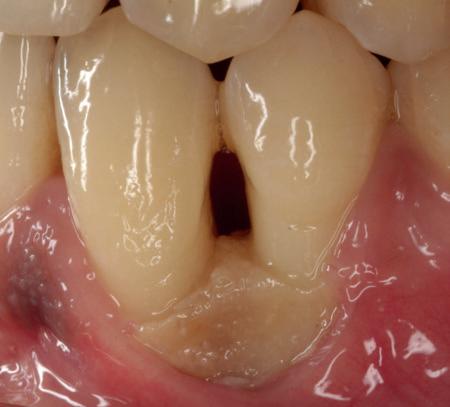

heeft de nadrukkelijke wens om geen brugconstructie te krijgen. Om die reden is een etsbrug of een conventionele brug geen optie. Daarom bestaat het behandelvoorstel uit vier losse kronen waarvan de 22 implantaat gedragen zal zijn. Een gedetailleerd onderzoek van de regio 22 is noodzakelijk (foto 4-6).

Uit het röntgenonderzoek blijkt dat op de locatie van de 22 veel bot verloren is gegaan en dat er niet direct een implantaat geplaatst kan worden. Om die reden is een botaugmentatie geïndiceerd. Wel zijn distaal van de 21 en mesiaal van de 23 de botpieken aanwezig die de papillen ondersteunen. Naast te weinig bot, is op de locatie 22 in bucco-linguale richting ook te weinig volume gingiva aanwezig. Daarom zal er tevens een soft tissue graft aangebracht worden. Tijdens deze behandeling wordt ook de recessie op de 23 zoveel mogelijk bedekt (foto 7 en 8).

De flap en graft worden met poly-propelene 6.0 hechtingen gefixeerd. De tijdelijke reconstructie wordt herplaatst (foto 17-20).

Na 4-6 weken kan het aangebrachte healing abutment worden vervangen door een tijdelijk abutment. Deze wordt aan de kunststof reconstructie verbonden om zo de gingiva ter plaatse van de 22 te vormen. Zo lijkt het of er geen implantaat maar nog steeds een wortel aanwezig is, wat het esthetisch eindresultaat ten goede zal komen (foto 21-23). Vanaf 4-6 maanden ziet het weefsel er gezond uit. Nu kan met de uiteindelijke restauratiefase worden gestart (foto 24 en 25).